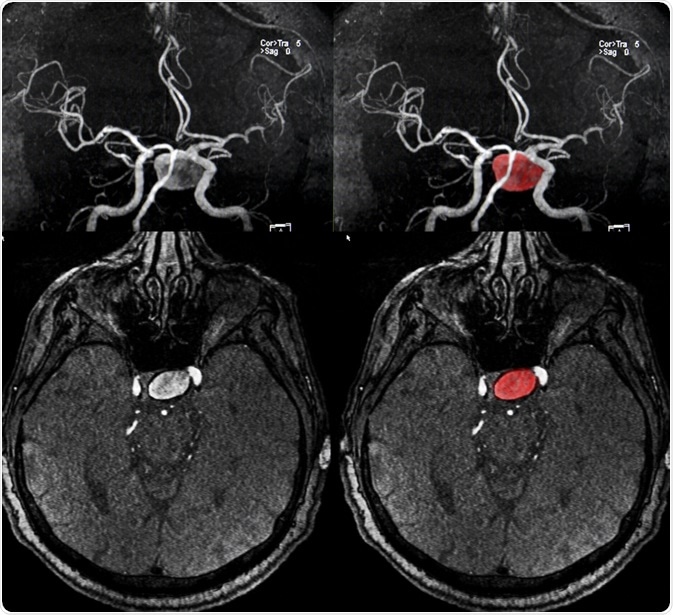

A brain (cerebral) aneurysm is a weak spot in an artery in the brain that swells and fills with blood.

Image Credit: Semnic / Shutterstock.com